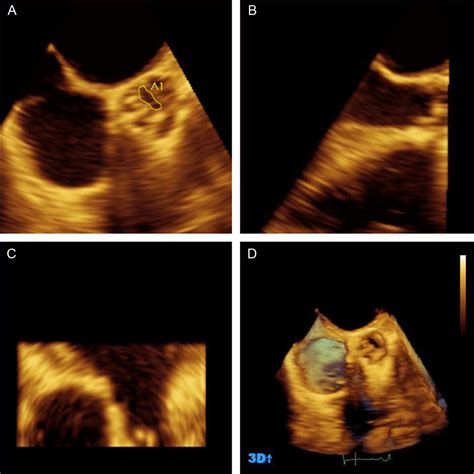

Physicians typically diagnose Severe Aortic Stenosis through a combination of physical examinations and advanced imaging technologies. The most common diagnostic tool is the echocardiogram, which provides a real-time visualization of the valve’s movement and measures the severity of the obstruction.

Transthoracic Echocardiogram (TTE) Valve area, pressure gradient, and left ventricular function.